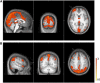

The blood-oxygen level dependent (BOLD) signals measured by functional magnetic resonance imaging (fMRI) are contaminated with noise from various physiological processes, such as spontaneous low-frequency oscillations (LFOs), respiration, and cardiac pulsation. These processes are coupled to the BOLD signal by different mechanisms, and represent variations with very different frequency content; however, because of the low sampling rate of fMRI, these signals are generally not separable by frequency, as the cardiac and respiratory waveforms alias into the LFO band. In this study, we investigated the spatial and temporal characteristics of the individual noise processes by conducting concurrent near-infrared spectroscopy (NIRS) and fMRI studies on six subjects during a resting state acquisition. Three time series corresponding to LFO, respiration, and cardiac pulsation were extracted by frequency from the NIRS signal (which has sufficient temporal resolution to critically sample the cardiac waveform) and used as regressors in a BOLD fMRI analysis. Our results suggest that LFO and cardiac signals modulate the BOLD signal independently through the circulatory system. The spatiotemporal evolution of the LFO signal in the BOLD data correlates with the global cerebral blood flow. Near-infrared spectroscopy can be used to partition these contributing factors and independently determine their contribution to the BOLD signal.